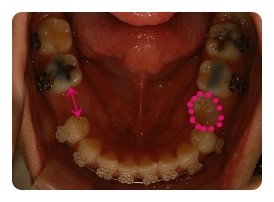

( 하악비교 )

▲ 발치전 - 왼쪽결손치, 오른쪽유치 1차삭제 예정

▲ 5월 - 스크류식립 후 본격적으로 하악당기기 1개월차

▲ 7월 - 3개월차, 오른쪽유치 2차삭제

▲ 10월 - 6개월차

물론 사진크기나 각도가 100% 일치하진않지만 최대한 비슷하게 비교해보려고 노력햇는데

어떤가요 ??

왼쪽 결손치는 발치한지 몇년되엇기때문에 이미 잇몸뼈가 굳어져서 진행이 더딜수밖에 없다고해요

그동안 꿈쩍도 안하고잇는줄 알앗는데 비교해보니 이정도면 뭐 기특하네요 ㅋㅋ

그에비해 오른쪽 유치는 조금씩 삭제하면서 당기고 잇는데요

쑥쑥 잘 움직여주고 잇어서 2차 삭제까지 햇는데도 벌써 또 닫혀가고 잇어요

아마도 다음에 가면 또 삭제할듯요 ;; 아 ~~~ 삭제할때의 시큰시큰한 느낌 시르다 ㅠㅠ